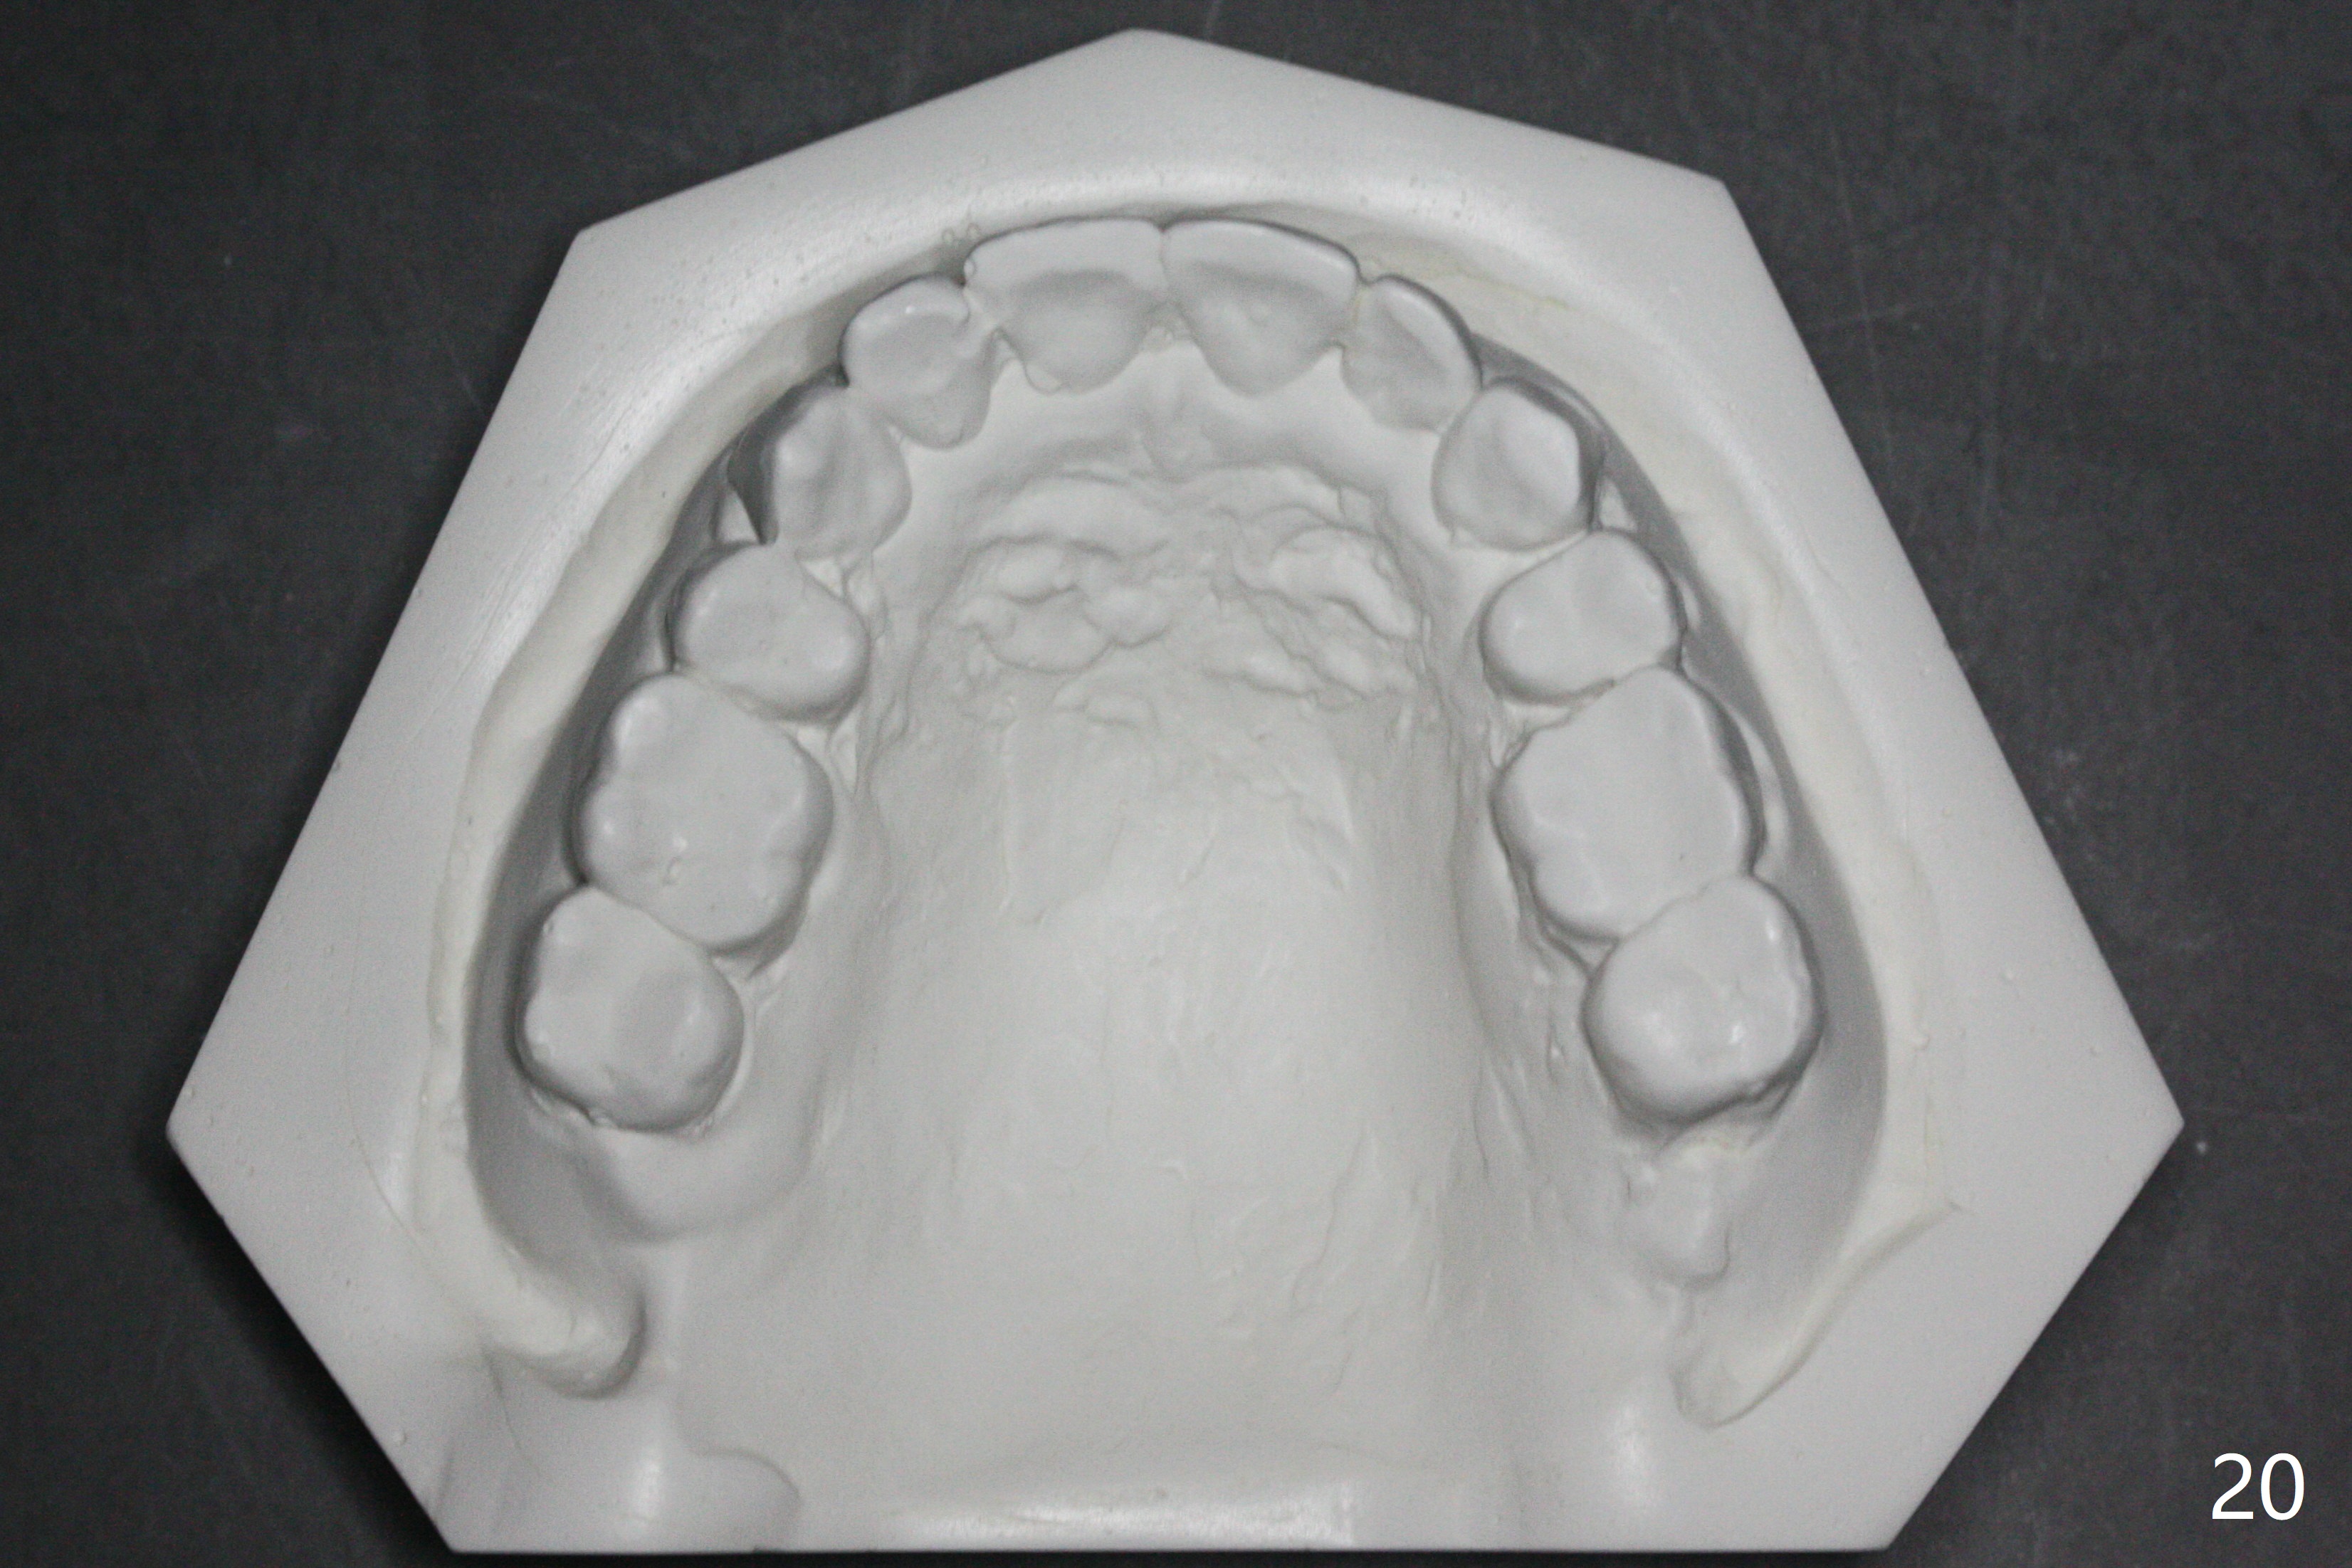

Enough Space For Crowding After Extraction? A 47-year-old man requests orthodontic treatment following SRP in other office (Fig.1-11). For severe crowding and midline shifting, extraction of four of the 1st bicuspids is imminent. Is it enough? To answer the question, model surgery is performed (Fig.12-16). 1st visit: periodontal maintenance, orthodontic consent (emphasizing oral hygiene) extract 4s and possibly L8s and separators. The beauty of this vist is that after local anesthesia and extraction including L8s, it is painless and easy to remove calculus from the proximal surfaces of the neighboring teeth. It is much easier to place separators after extraction. It is expected that there is no gingival erythema when the patient returns for bracketing. Take photos of UR3, similar to Fig.3. Molar banding is also anticipated to be easy with separator placement after extraction. Return to Ortho Cases Xin Wei, DDS, PhD, MS 1st edition 11/23/2017, last revision 04/28/2019